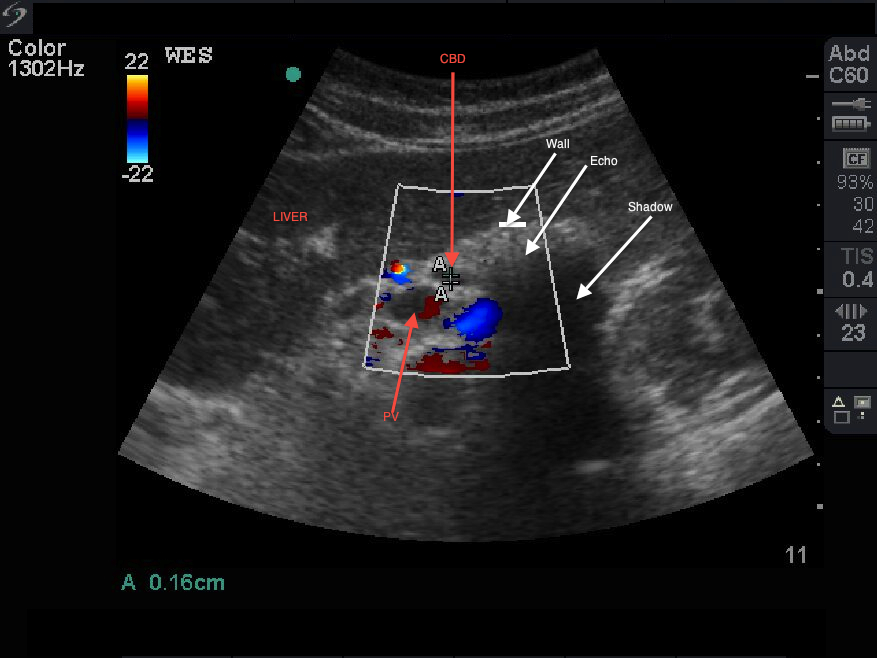

Porcelain gallbladder. Ultrasound image showing contracted gallbladder... Download Scientific Porcelain Gallbladder Images Porcelain gallbladder or calcified gallbladder or cholecys topathia chronica calcarea is a relatively rare condition with an incidence rate of 0.06 to. Porcelain gallbladder is a rare condition where calcium builds up on the gallbladder walls. The wall becomes brittle, hard, and often takes on a bluish hue. It leads to a brittle, hard lining in the gallbladder and may. Porcelain Gallbladder Images.